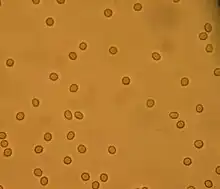

- Urinalysis - After the patient provides a urine specimen, it is sent to the lab for analysis using a variety of methods including urine dipstick testing and microscopic examination. Because the kidney is responsible for making urine, analyzing the urine directly can provide crucial data that can help the physician diagnose nephritic syndrome.[33] Some findings on urinalysis that are consistent with nephritic syndrome include red blood cells (hematuria), red blood cell casts, proteinuria, and possibly white blood cells (pyuria).[9]